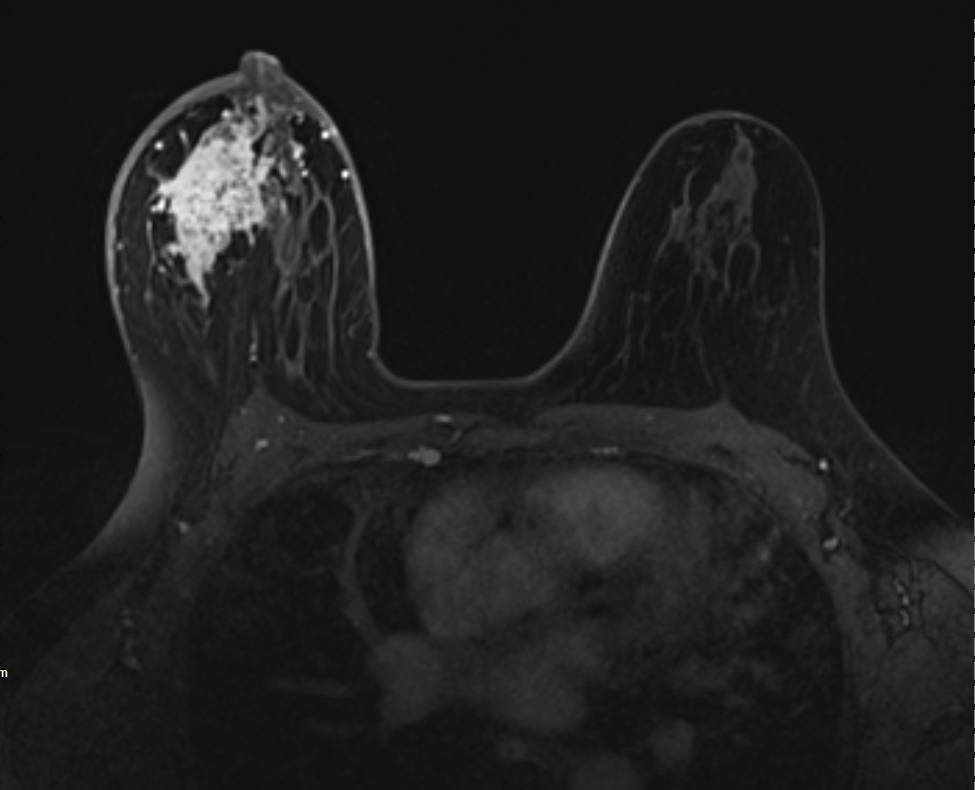

9、乳腺數(shù)字化攝影、乳管造影、乳腺磁共振檢查;

9、乳腺數(shù)字化攝影廣泛應(yīng)用于乳腺疾病的篩查、診斷;乳腺磁共振對(duì)于診斷乳腺的各種良惡性疾病,尤其對(duì)于早期乳腺癌的檢出具有明顯的優(yōu)越性。

右側(cè)乳腺浸潤(rùn)性癌